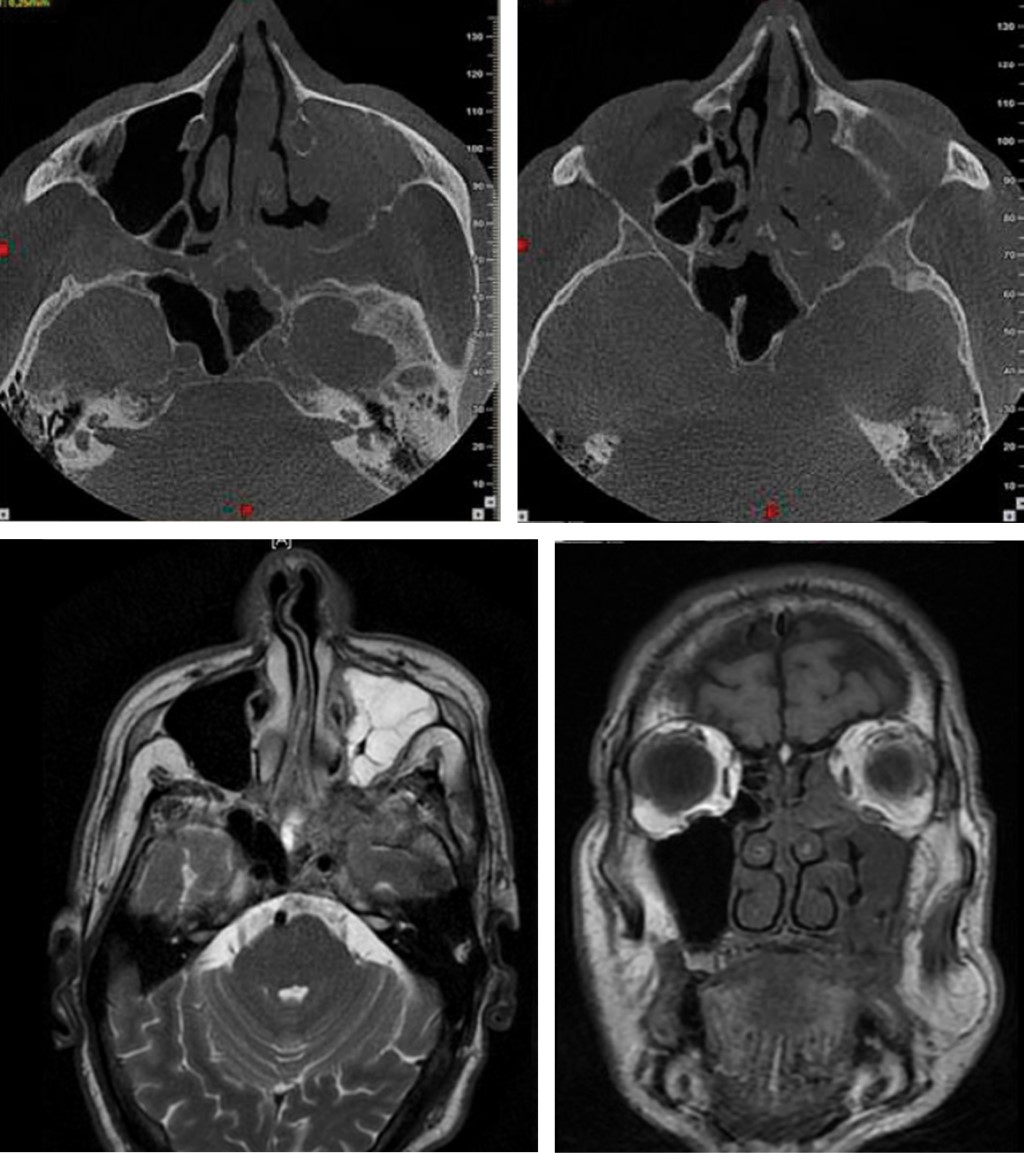

The CT of the skull and face is isodense in the left maxillary sinus, extended to the left ethmoid cells, left nasal turbinates (superior, middle and inferior) and sphenoid sinus. In magnetic resonance it was evidenced in the T2 window sequence hyperintense image in the left maxillary sinus with hypointense areas, as for the isointense image T1 window sequence with hypointense areas in the left maxillary sinus with extension along the left orbital floor, as well as in the Ipsilateral ethmoid and sphenoid sinuses, no brain tissue injury was observed (Figure 3). Patient is admitted to the "Dr. Ángel Larralde" University Hospital in charge of the Internal Medicine, Infectology and Oral and Maxillofacial Surgery Service, for surgical medical management.

In a CT of the skull prior to surgery, a reduction of the maxillary sinus lesion is observed, but the ethmoid region, sphenoid region on the left side and involvement of the floor and medial wall of the orbit are still taken.

A sample is taken for mycological study of the maxillary, ethmoidal and left sphenoid sinus region with KOH, Chinese ink (negative staining) and mycological culture at 28 and 37 oC which reported: no observation of fungal forms in examined samples. The post-operative CT of the skull and face revealed a type III bone defect according to Brown and Shaw after left hemimaxylectomy, as well as improvement and reduction of the lesion in the region of the ethmoid and sphenoid sinus and the region of the medial wall of the left orbit (Figure 4).

Figure 3